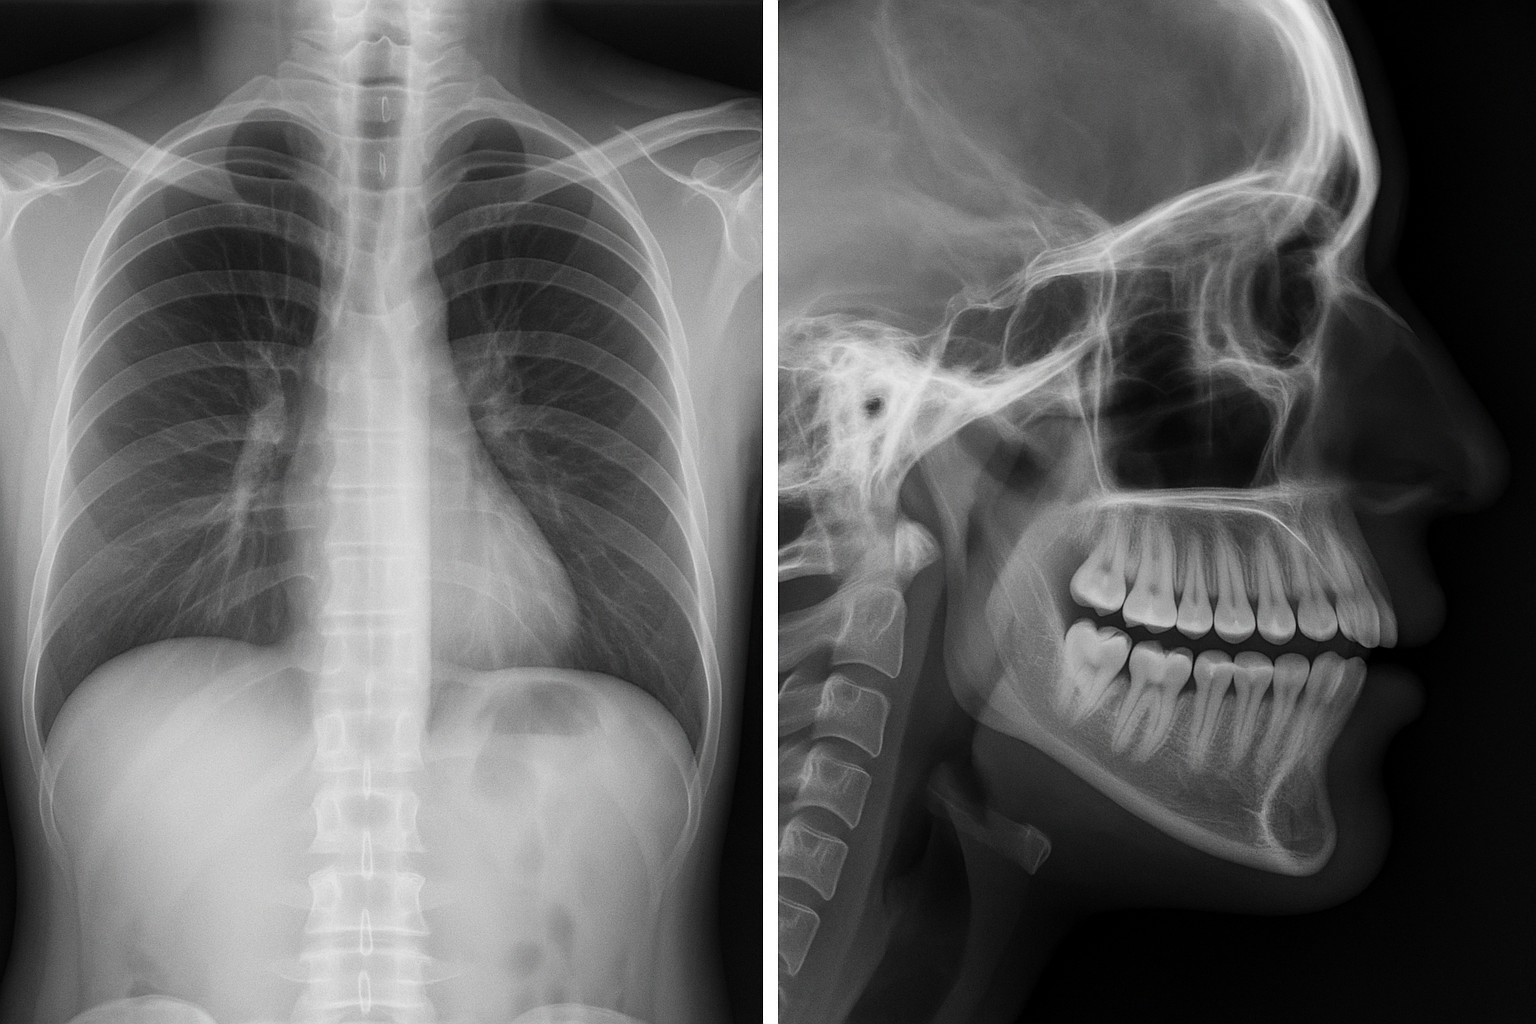

Raio-X Convencional

Exames radiográficos tradicionais para diagnósticos rápidos e eficazes